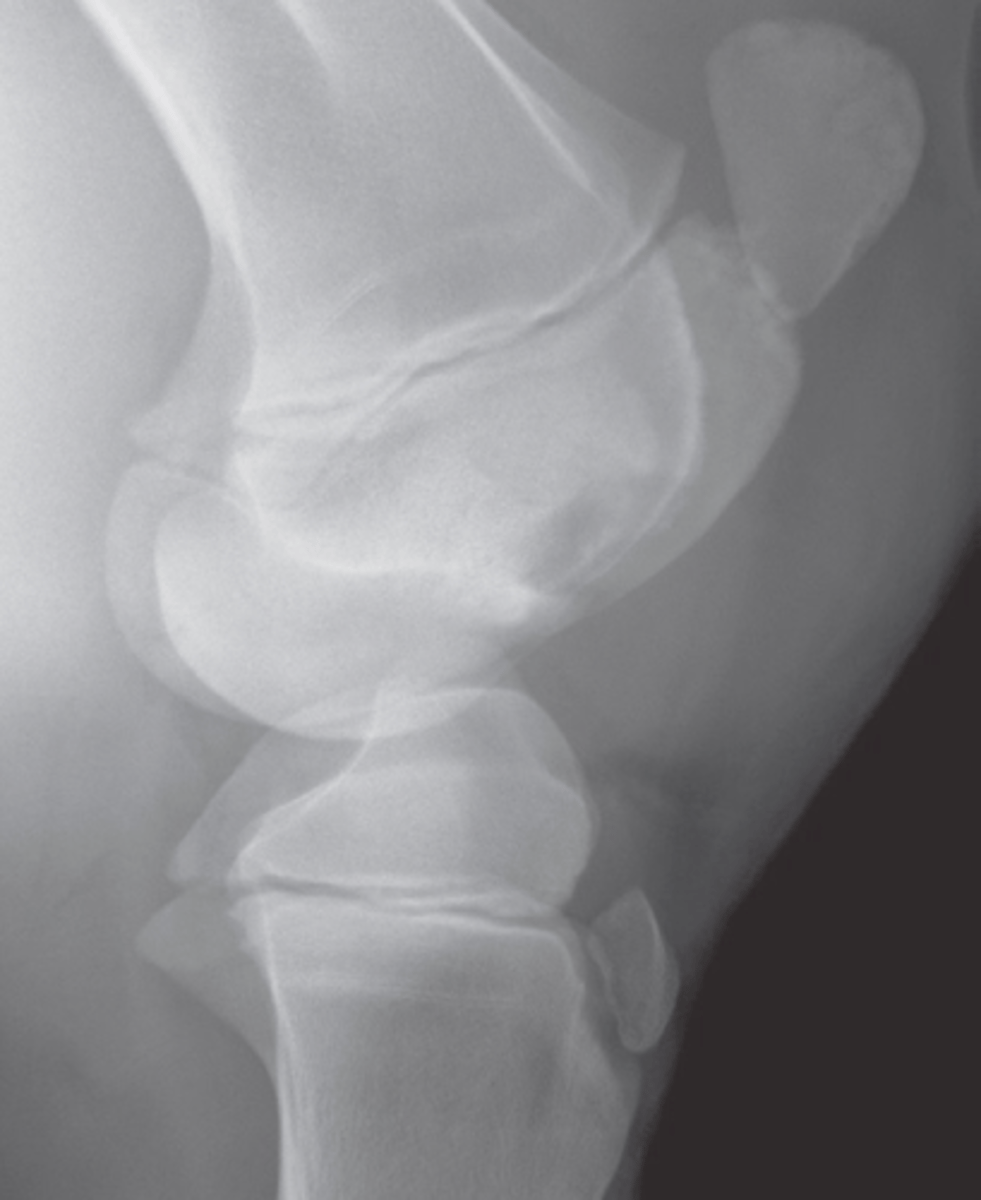

Epiphyseal

Identify the type of infection?